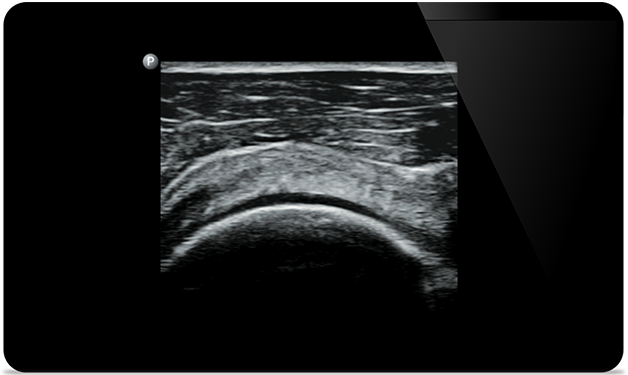

Lumify helpt u de fijne details in spieren, gewrichten, ligamenten, pezen en kraakbeen te zien om een nauwkeurigere diagnose te kunnen stellen.

Lumify kan u helpen patiënten van top tot teen te beoordelen, of het nu gaat om fasciitis plantaris, tendinitis of bursitis in de ligamentum patellae, of zelfs schouderinstabiliteit in de rotatorenmanchet.

SonoCT versterkt de beeldvorming van het echte weefsel, terwijl willekeurige artefacten worden geëlimineerd. Deze technologie produceert beelden die beter zijn dan conventionele beeldvorming bij tot wel 94% van de patiënten.